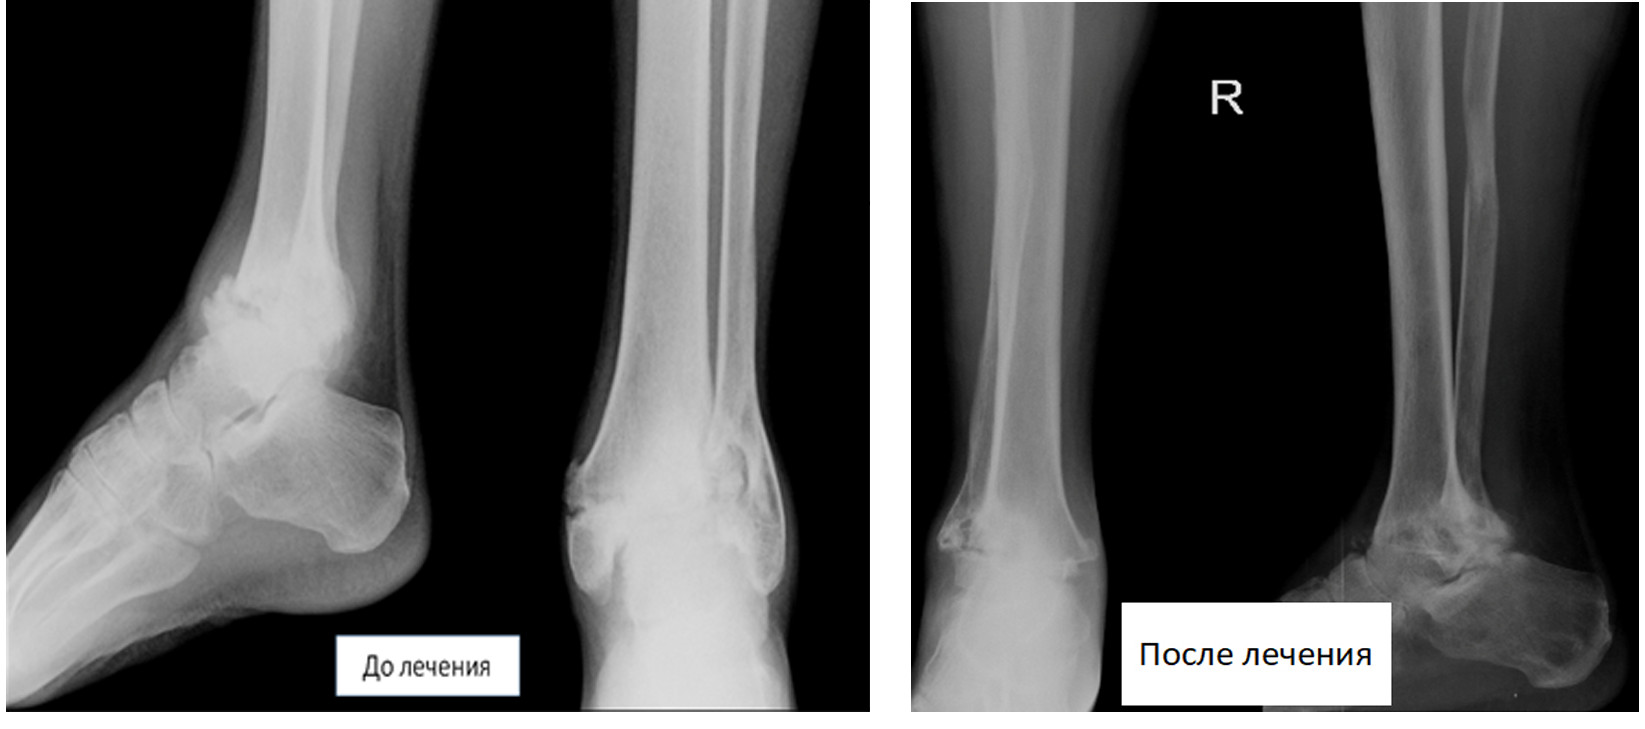

Пациент 32 лет обратился с посттравматическим артрозом правого голеностопного сустава. До обращения пациент неоднократно лечился в различных медучреждениях, где ему проводилось медикаментозное лечение, внутрисуставное введение препаратов гиалуроновой кислоты. После каждого курса лечения в течение 3-5 мес боли в области сустава уменьшались, а затем вновь усиливались. При рентгенологическом обследовании у пациента было выявлено полное разрушение голеностопного сустава. В связи с длительным неэффективным лечением и постоянными сильными болями пациенту в государственной больнице было предложено выполнить ампутацию на уровне голени.

Нами было выполнено оперативное лечение, направленное на сохранение конечности. В настоящее время пациент активно пользуется своей ногой. Ходит практически не прихрамывая. Вернулся к прежней работе.